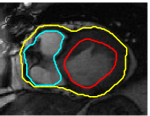

V-D Multiple Region Segmentation: Full Heart Segmentation

We now demonstrate our approach in performing challenging full heart segmentation: segmentation of the ventricles and epicardium all in one shot. Both the RV and epicardium are especially challenging as the contrast of the RV and background is subtle in comparison to the LV, and the myocardium wall near parts of the RV is very thin. We are not aware of another interactive method that is able to segment all structures, and so we compare to Medviso even though the method is not specifically tailored to the myocardium, but the method is generic and is able to propagate a segmentation. Further, Medviso does not segment multiple regions all at once and thus we perform separate segmentation of the LV, RV and epicardium. Since ground truth is not available for the outer wall of the myocardium in any standard dataset that we aware of, we show visual comparison.

Figure 10 shows the slice-wise results of our method and Medviso on a full 3D cardiac MRI sequence for a full cardiac cycle. Results indicate that our method is more accurate in capturing the shape of the ventricles and epicardium, and our method is especially more promising on the RV and epicardium. Figure 11 shows visualization of the results in 3D, and that our method more accurately resembles the structure of the heart.